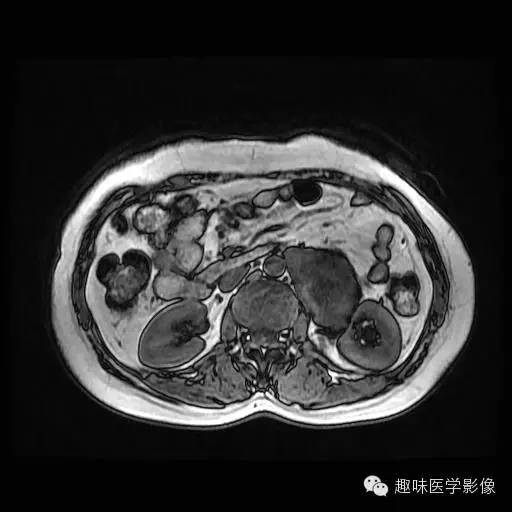

女,45岁,因“外伤致左腰腹部疼痛22天”入院。

左侧肾窦、肾盂及输尿管壶腹部见约44*79毫米的长及稍长T1、长及稍长T2囊实性异常信号影,内可见分隔,DWI显示实性成分为高信号,反相位图像病变信号无明显减低;皮质期实性部分呈轻度异常强化,髓质期及延迟期呈轻至中度异常强化;囊性成分无强化;肾盏轻度扩张,内可见长T1长T2信号影;左侧肾实质未见明显异常信号。两侧肾静脉及下腔静脉未见明显右侧肾脏、两侧肾上腺未见异常,肝门、肾门及所见腹膜后未见明显肿大淋巴结影。